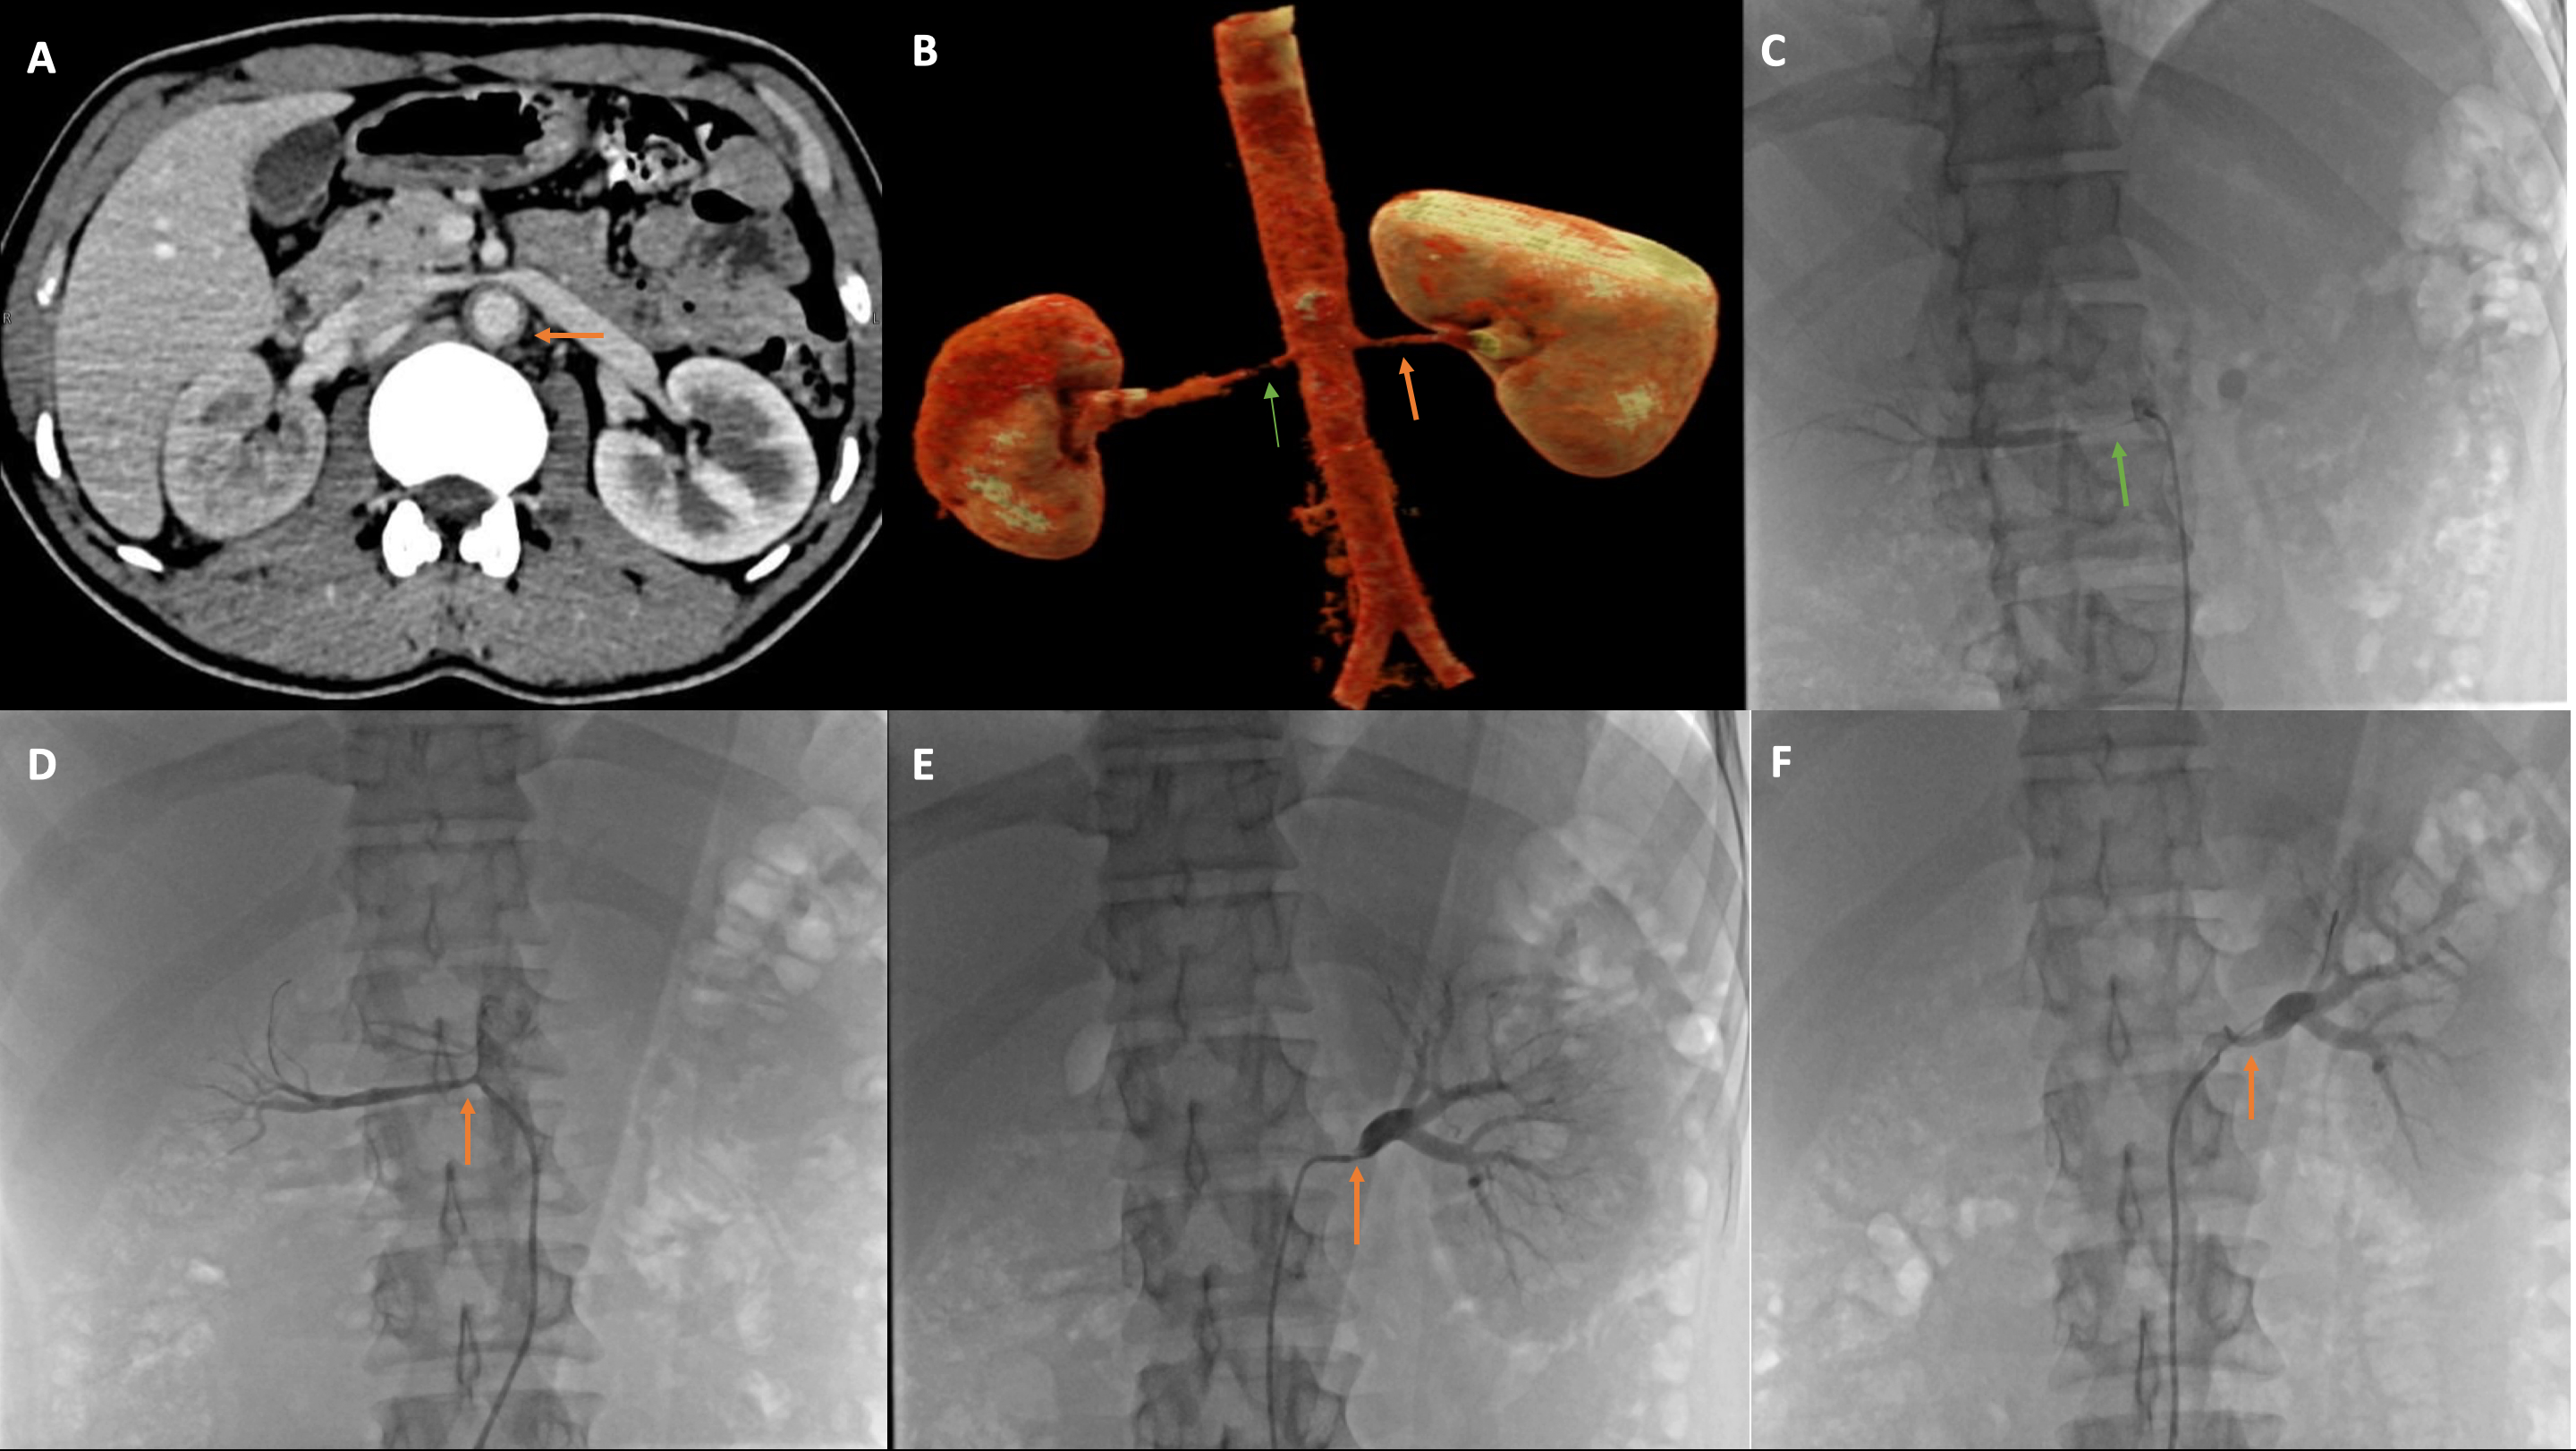

Peripheral Angiography

Peripheral Angiography in Jaipur – Dr. Anil Kumar Choudhary If you're experiencing leg pain while walking, numbness, non-healing wounds, or signs of poor circulation, it may be time to get a Peripheral Angiography done. Dr. Anil Kumar Choudhary, the best interventional cardiologist in Jaipur, offers advanced and accurate peripheral angiography to diagnose blockages in arteries outside the heart. With years of expertise in interventional and vascular cardiology, Dr. Choudhary has helped hundreds of patients identify and treat Peripheral Artery Disease (PAD) and other vascular conditions through timely diagnosis using this minimally invasive test. 🔍 What is Peripheral Angiography? Peripheral Angiography is a specialized diagnostic test that uses X-ray imaging and a contrast dye to visualize the blood flow in arteries supplying the legs, arms, kidneys, neck (carotid), or abdomen. It helps detect narrowed or blocked arteries, allowing precise planning of interventional treatments like angioplasty or stenting. 🩺 When is Peripheral Angiography Needed? Peripheral Angiography is commonly recommended if you are experiencing: Leg pain or cramping while walking (claudication) Cold or discolored limbs Non-healing foot ulcers or wounds Poor circulation in arms or legs Suspected Peripheral Artery Disease (PAD) High risk of stroke (carotid artery blockages) Uncontrolled high blood pressure due to renal artery stenosis Diabetic foot or vascular complications 🏥 How Dr. Anil Kumar Choudhary Performs Peripheral Angiography Dr. Anil Kumar Choudhary performs the procedure in a modern Cath Lab setting, using high-resolution imaging and advanced catheter techniques. A contrast dye is injected through a small catheter, usually inserted in the groin or wrist, and detailed X-ray images of the peripheral arteries are taken. The test is: Minimally invasive Painless and safe Takes 30–60 minutes Often followed by treatment (like angioplasty) in the same sitting if a blockage is found 💡 Why Choose Dr. Anil Kumar Choudhary for Peripheral Angiography in Jaipur? ✅ Best Interventional Cardiologist in Jaipur with vast experience in vascular diagnostics 📊 Expert in detecting complex arterial blockages with precision 🏥 Performs procedures in a high-end cath lab equipped with advanced imaging 💼 Offers complete care – from diagnosis to treatment (angioplasty or stenting) 🩺 Trusted by patients for his accurate reporting, ethical practice, and personalized approach 💉 Conditions Diagnosed with Peripheral Angiography: Peripheral Artery Disease (PAD) Carotid Artery Disease Renal Artery Stenosis Aorto-iliac Occlusive Disease Diabetic Vascular Complications Arm or Leg Artery Blockages Claudication and Critical Limb Ischemia 🌟 Best Cardiologist in Jaipur for Vascular Diagnosis and Care With unmatched experience in vascular imaging and interventional cardiology, Dr. Anil Kumar Choudhary ensures timely diagnosis and the most appropriate treatment strategy for patients with vascular blockages and circulation issues.